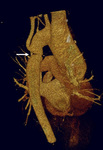

Abdominal coarctation

N. Pal, D. McEneaney. BMJ Case Reports, 2009